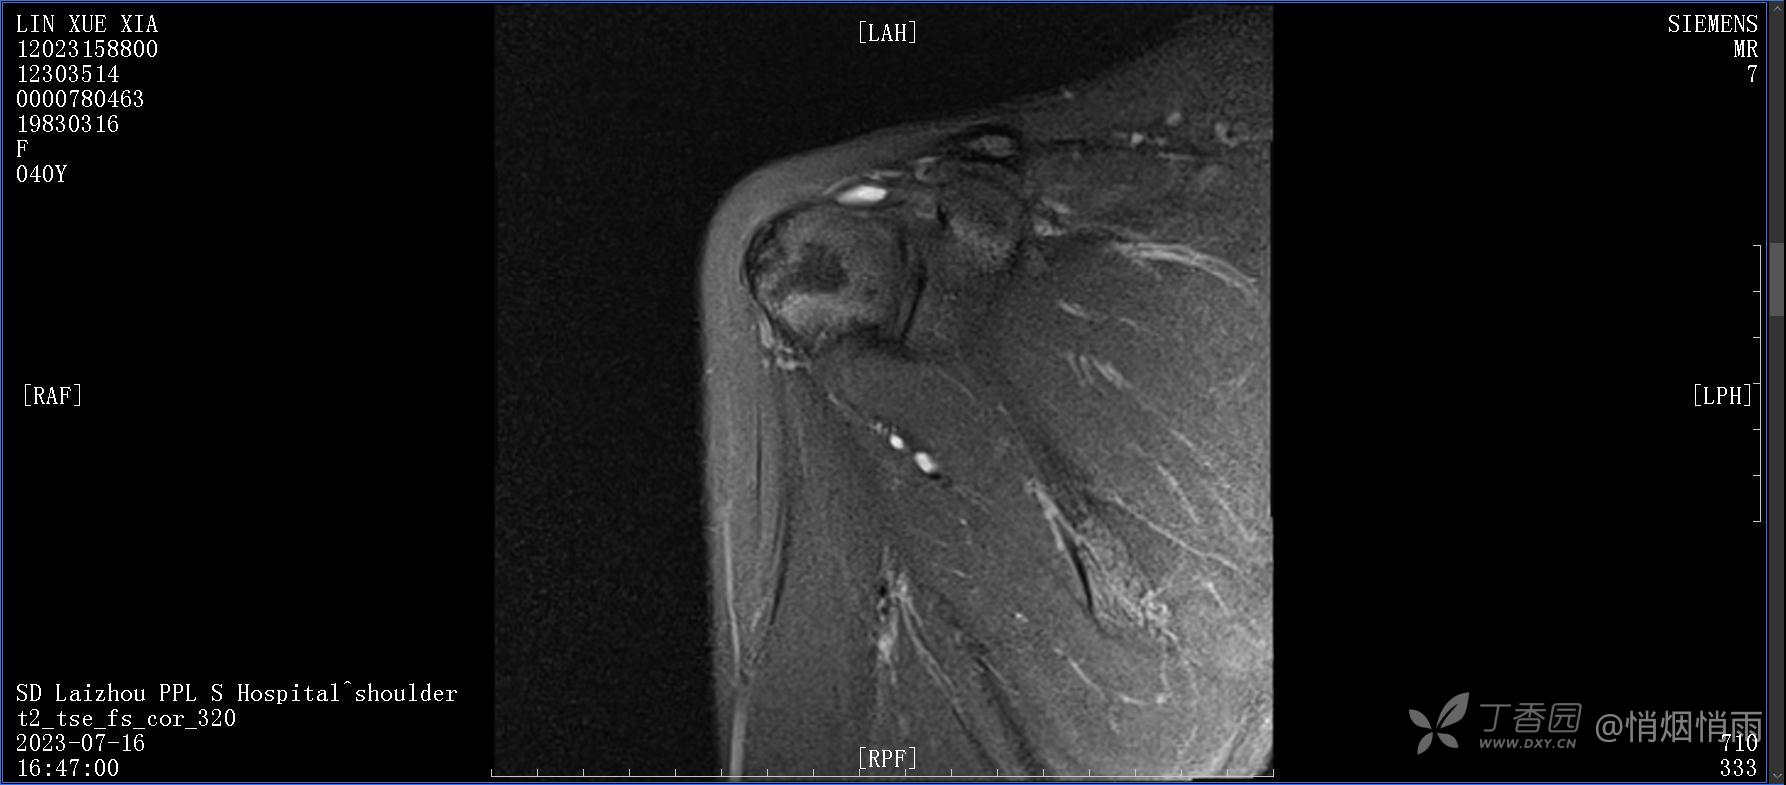

查体:右肩关节局部轻度肿胀,肩胛区压痛明显,痛处不固定,肩关节痛性活动受限,jobe test(+),lift -off test(+),中指、环指感觉较余指减退,余肢端感觉及血运情况可。

目前的诊断,暂时依据辅助检查诊为肩袖损伤,但是患者疼痛的性质和特点,却不是单纯的肩袖损伤所致。考虑过胸廓出口综合征,但是该疾病会出现肩胛区的疼痛吗?(由于考虑到费用的问题,没再进行下一步的检查)带状疱疹会有如此的症状吗?